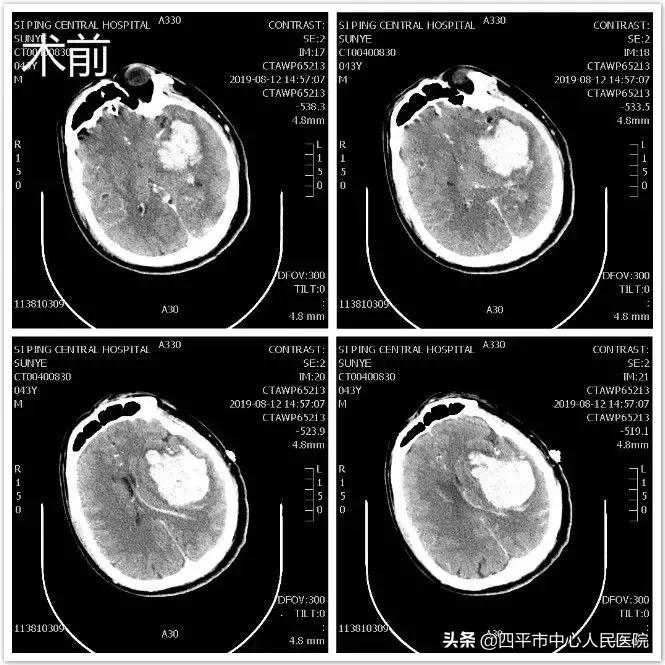

Case 5 左侧脑出血,发现左侧后交通动脉未破裂动脉瘤

患者孙XX,入院前约21小时无明显诱因突发言语不清伴右侧肢体活动不灵,表现为肢体瘫痪,既往高血压病史约10年,最高可达180mmHg,不规律服用降压药物急被家属送至我院就诊,急送我院急诊给予查头部CT后,示脑出血。患者入院后病情呈进行性加重,患者符合手术指征,行头部CT定位见出血量增加,头部CTA示相当于左侧后交通动脉起始部小动脉瘤,李晓东主任带领马龙医生在清除脑出血的同时将动脉瘤夹闭,出院时,患者病情平稳,预后较好。